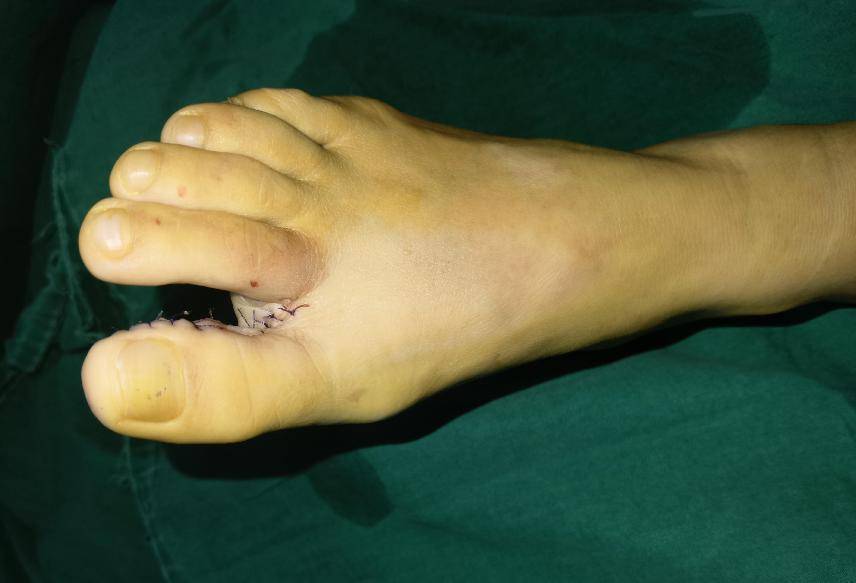

一般情况下手指外伤残端谨慎短缩修整,尽量保留现有的指骨,甲床和关节

临床上要根据残指的长度,残端情况,以及患者的年龄

人,于10个月前因外伤损伤左手中指,在当地医院行"左手中指残端修整术"